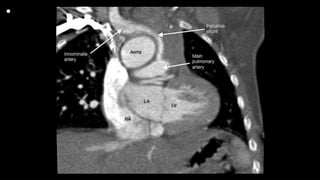

• All MBT shunt procedures were performed via upper

ministernotomy. A small skin incision was made from 0.5 cm

below the suprasternal notch to 1 cm below the sternal

was dissected.

• The systemic site of the shunt insertion was either the innominate or right

subclavian artery, and the site of the distal anastomosis was the right

pulmonary artery as close to the middle line as possible.